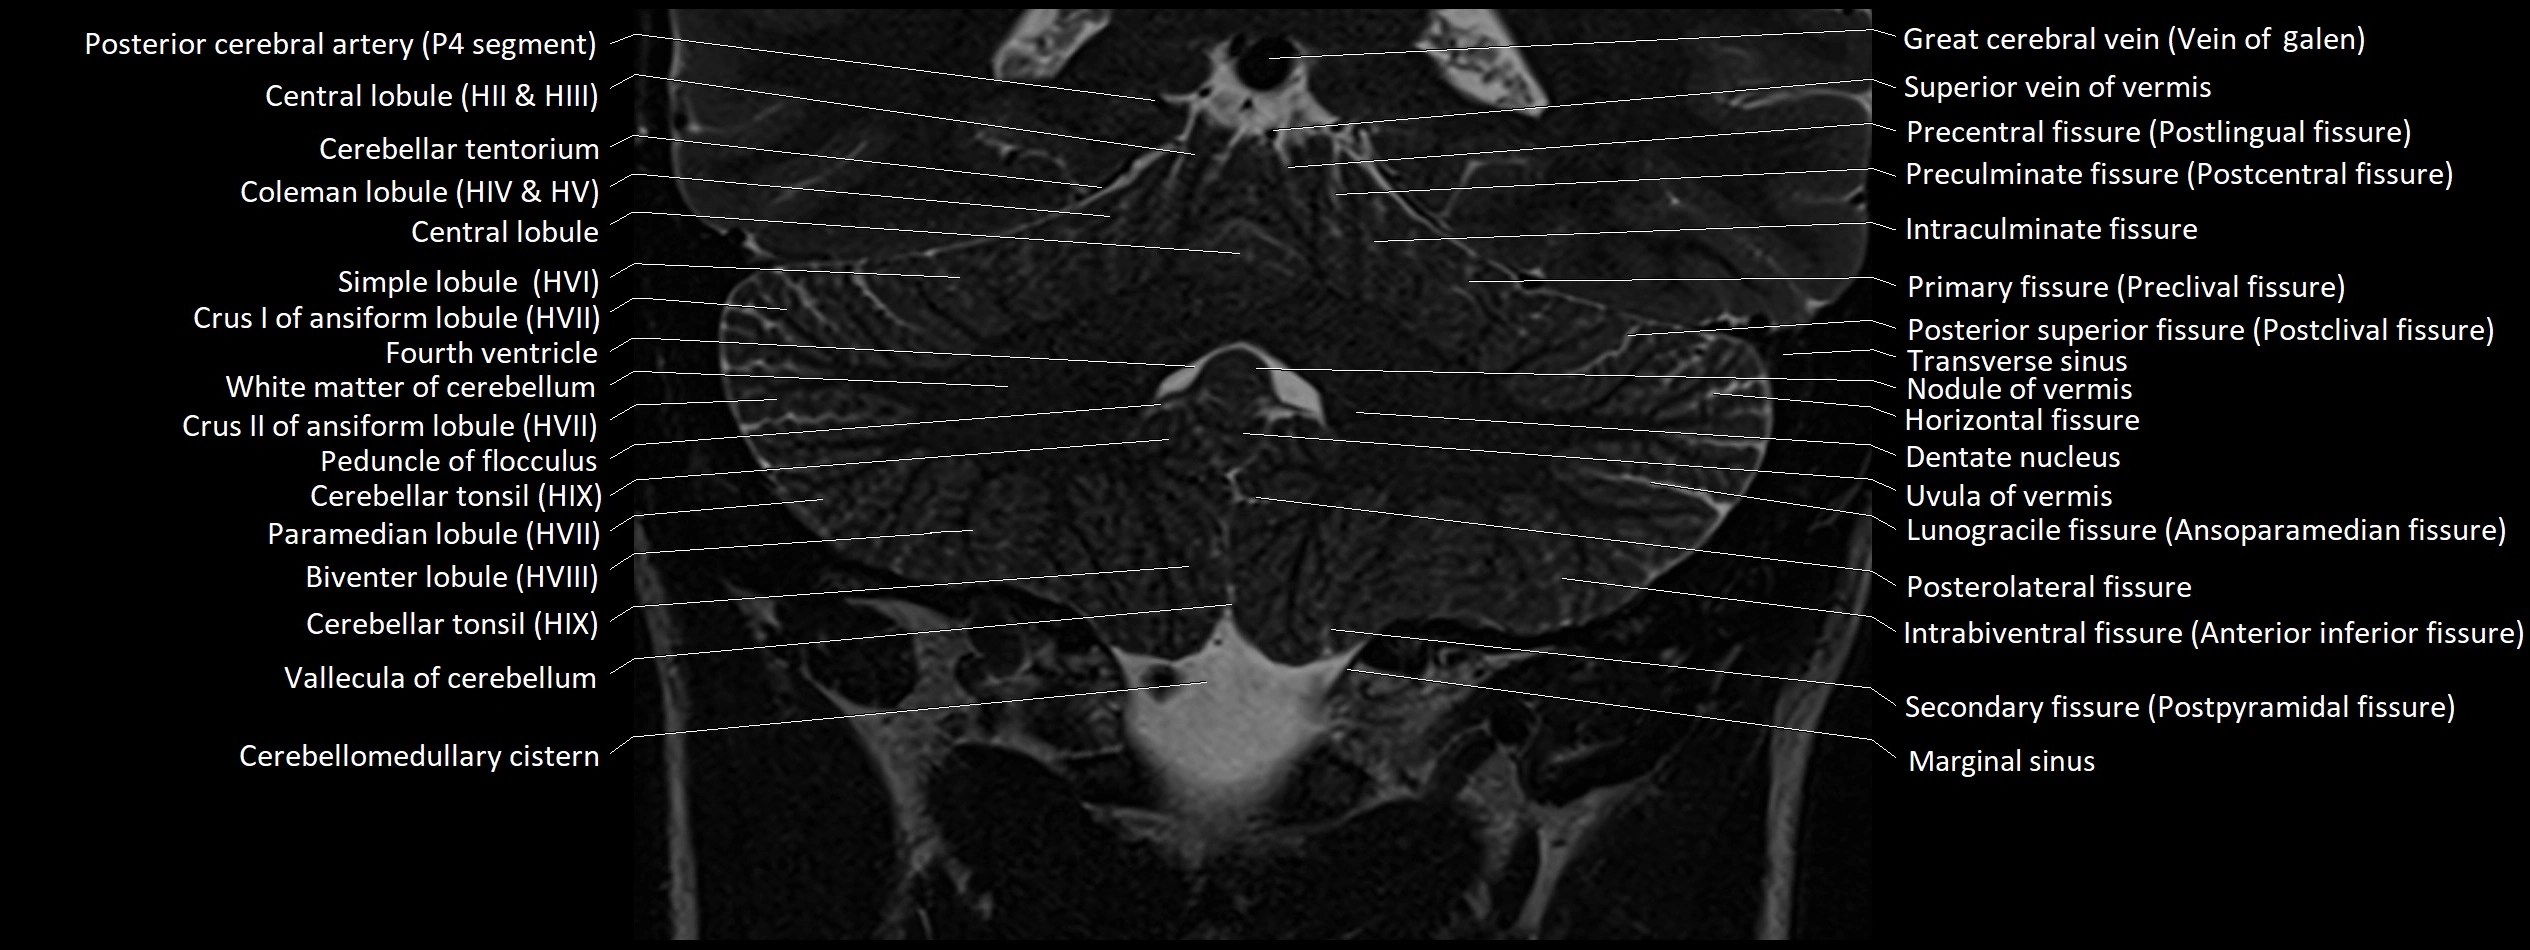

MRI images